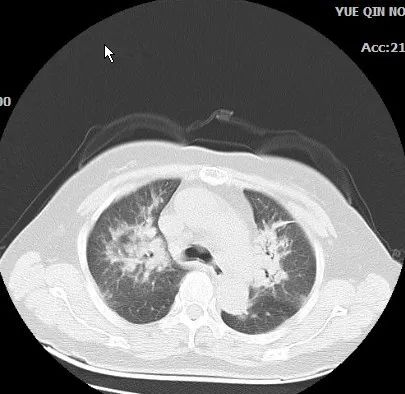

患者抗感染治疗后咳嗽症状好转,某天体温稳定,要求出院,予出院,建议出院后门诊复查肺部CT。1个月后患者门诊复查肺部CT发现两肺新增感染。

图4 肺部CT(20210615)

图5 肺部CT(20210615)

图6 肺部CT(20210615)

患者游走性肺炎,需考虑:支原体肺炎、机化性肺炎、过敏性肺炎、嗜酸细胞性肺炎、肺梗死、脓毒肺栓塞、反复误吸、活动性异物或肿瘤、肺血管炎。

再次予支气管镜下活检示:机化性肺炎,予甲泼尼龙片治疗后,肺部病灶吸收好转。

该病例提示,能找到病灶的不明原因发热,要注意随访,如随访病灶无好转需进一步病原学检查,发热不只是感染所致,非感染性疾病非结缔组织疾病也可导致发热;而铁蛋白>500ng/mL对于非感染性发热有诊断价值[4]。